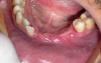

Case reportJ.L.O., a 38-year-old patient was referred to treatment experiencing an extensive lesion involving anterior portion of lower alveolar border with a 10-year progress history. Upon extraoral examination, patient's difficult labial sealing was noticeable by virtue of change in the lower third of the face due to intraoral growth of the lesion. Intraoral clinical evaluation revealed a large-sized lesion involving the anterior portion of the mandible, promoting displacement of teeth 41, 31, 32, 33 and 34 (Fig. 1). Similarly, dental displacement was radiographically clear and the lesion presented slight radiopacity (Fig. 2). Despite the lesion being covered by intact mucosa of normal color, during planning we chose to perform an incisional biopsy prior to definite surgical treatment, by which diagnosis was of inflammatory fibrous hyperplasia. Surgical Access occurred through a wedge incision surrounding the lesion, associated with intrasulcular incision in involved teeth and tissue displacement was performed with the aid of a Molt separator (Fig. 3). Following complete removal of the lesion, dental extraction of involved teeth was performed since they presented compromise of supporting periodontium (Fig. 4). Tissue was repositioned using 5-0 Polypropylene wire and the piece was sent to histopathological examination. Lesion was microscopically described by the presence of dense fibrous connective tissue with multiple vital bone trabeculae, surrounded by uneven pavimentous epithelium (Fig. 5). The presence of mixed inflammatory infiltrate was also seen. In addition to routine HE staining, immunohistochemistry was performed for actin in smooth muscle tissue, in which positivity to HHF-35 was observed (Fig. 6), thus confirming myofibroblastic characteristic of the lesion. Therefore, the diagnosis of excisional biopsy was peripheral ossifying fibroma. The patient recovered with no incidents and clinical and radiographic 12-month follow-up revealed absence of relapses (Figs. 7 and 8).

Upon clinical examination, the lesion is often described as a pedunculated or sessile nodular mass,3 and sessile-based is the most frequent presence.5 Regarding location, 50% of the lesions affect the region of incisors and more than half of it is located in upper arch (60%).14 Single lesions are the most frequent ones1; despite that Kumar et al. (2006)7 have described a multisite case. In this context, with respect to location, the lesion hereof may be considered as having an atypical location because it affects lower arch. However, regarding positioning in the arch and lonesome appearance, it is in compliance with literature reports because it presented as a single lesion affecting anterior portions of lower border. Other authors have also occasionally described peripheral ossifying fibromas in sites different from the most common ones. Pal et al. (2012),4 for instance, described a lesion affecting the posterior portion of the mandible.

Regarding the extension of the lesion, in most cases, the longest length does not exceed 1.5cm.4,10 On the other hand, in this clinical case, authors described a peripheral ossifying fibroma that outstands for its large size, which is 3.5cm in its longest extension. Similarly, some authors have occasionally described larger lesions, with case reports of peripheral ossifying fibromas from 6 to 9cm.2,15 Sometimes, especially in cases of larger lesions, ectopic eruption, migration, and separation of teeth have been reported, as well as bone destruction.1,6,16 These uncommon aggressive characteristics were seen in this case report, where massive growth of the lesion has caused destruction of tissue supporting the teeth involved, as well as its migration, which did not allow their maintenance after total exeresis of the lesion.